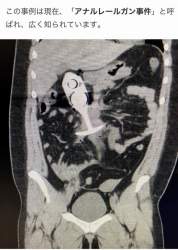

>アナルレールガン事件

「自分が診た患者の中でもっとも酷い人体破壊の例だった」

70906 B

>広く知られています。

>「自分が診た患者の中でもっとも酷い人体破壊の例だった」

これマジで内蔵グチャグチャじゃない?